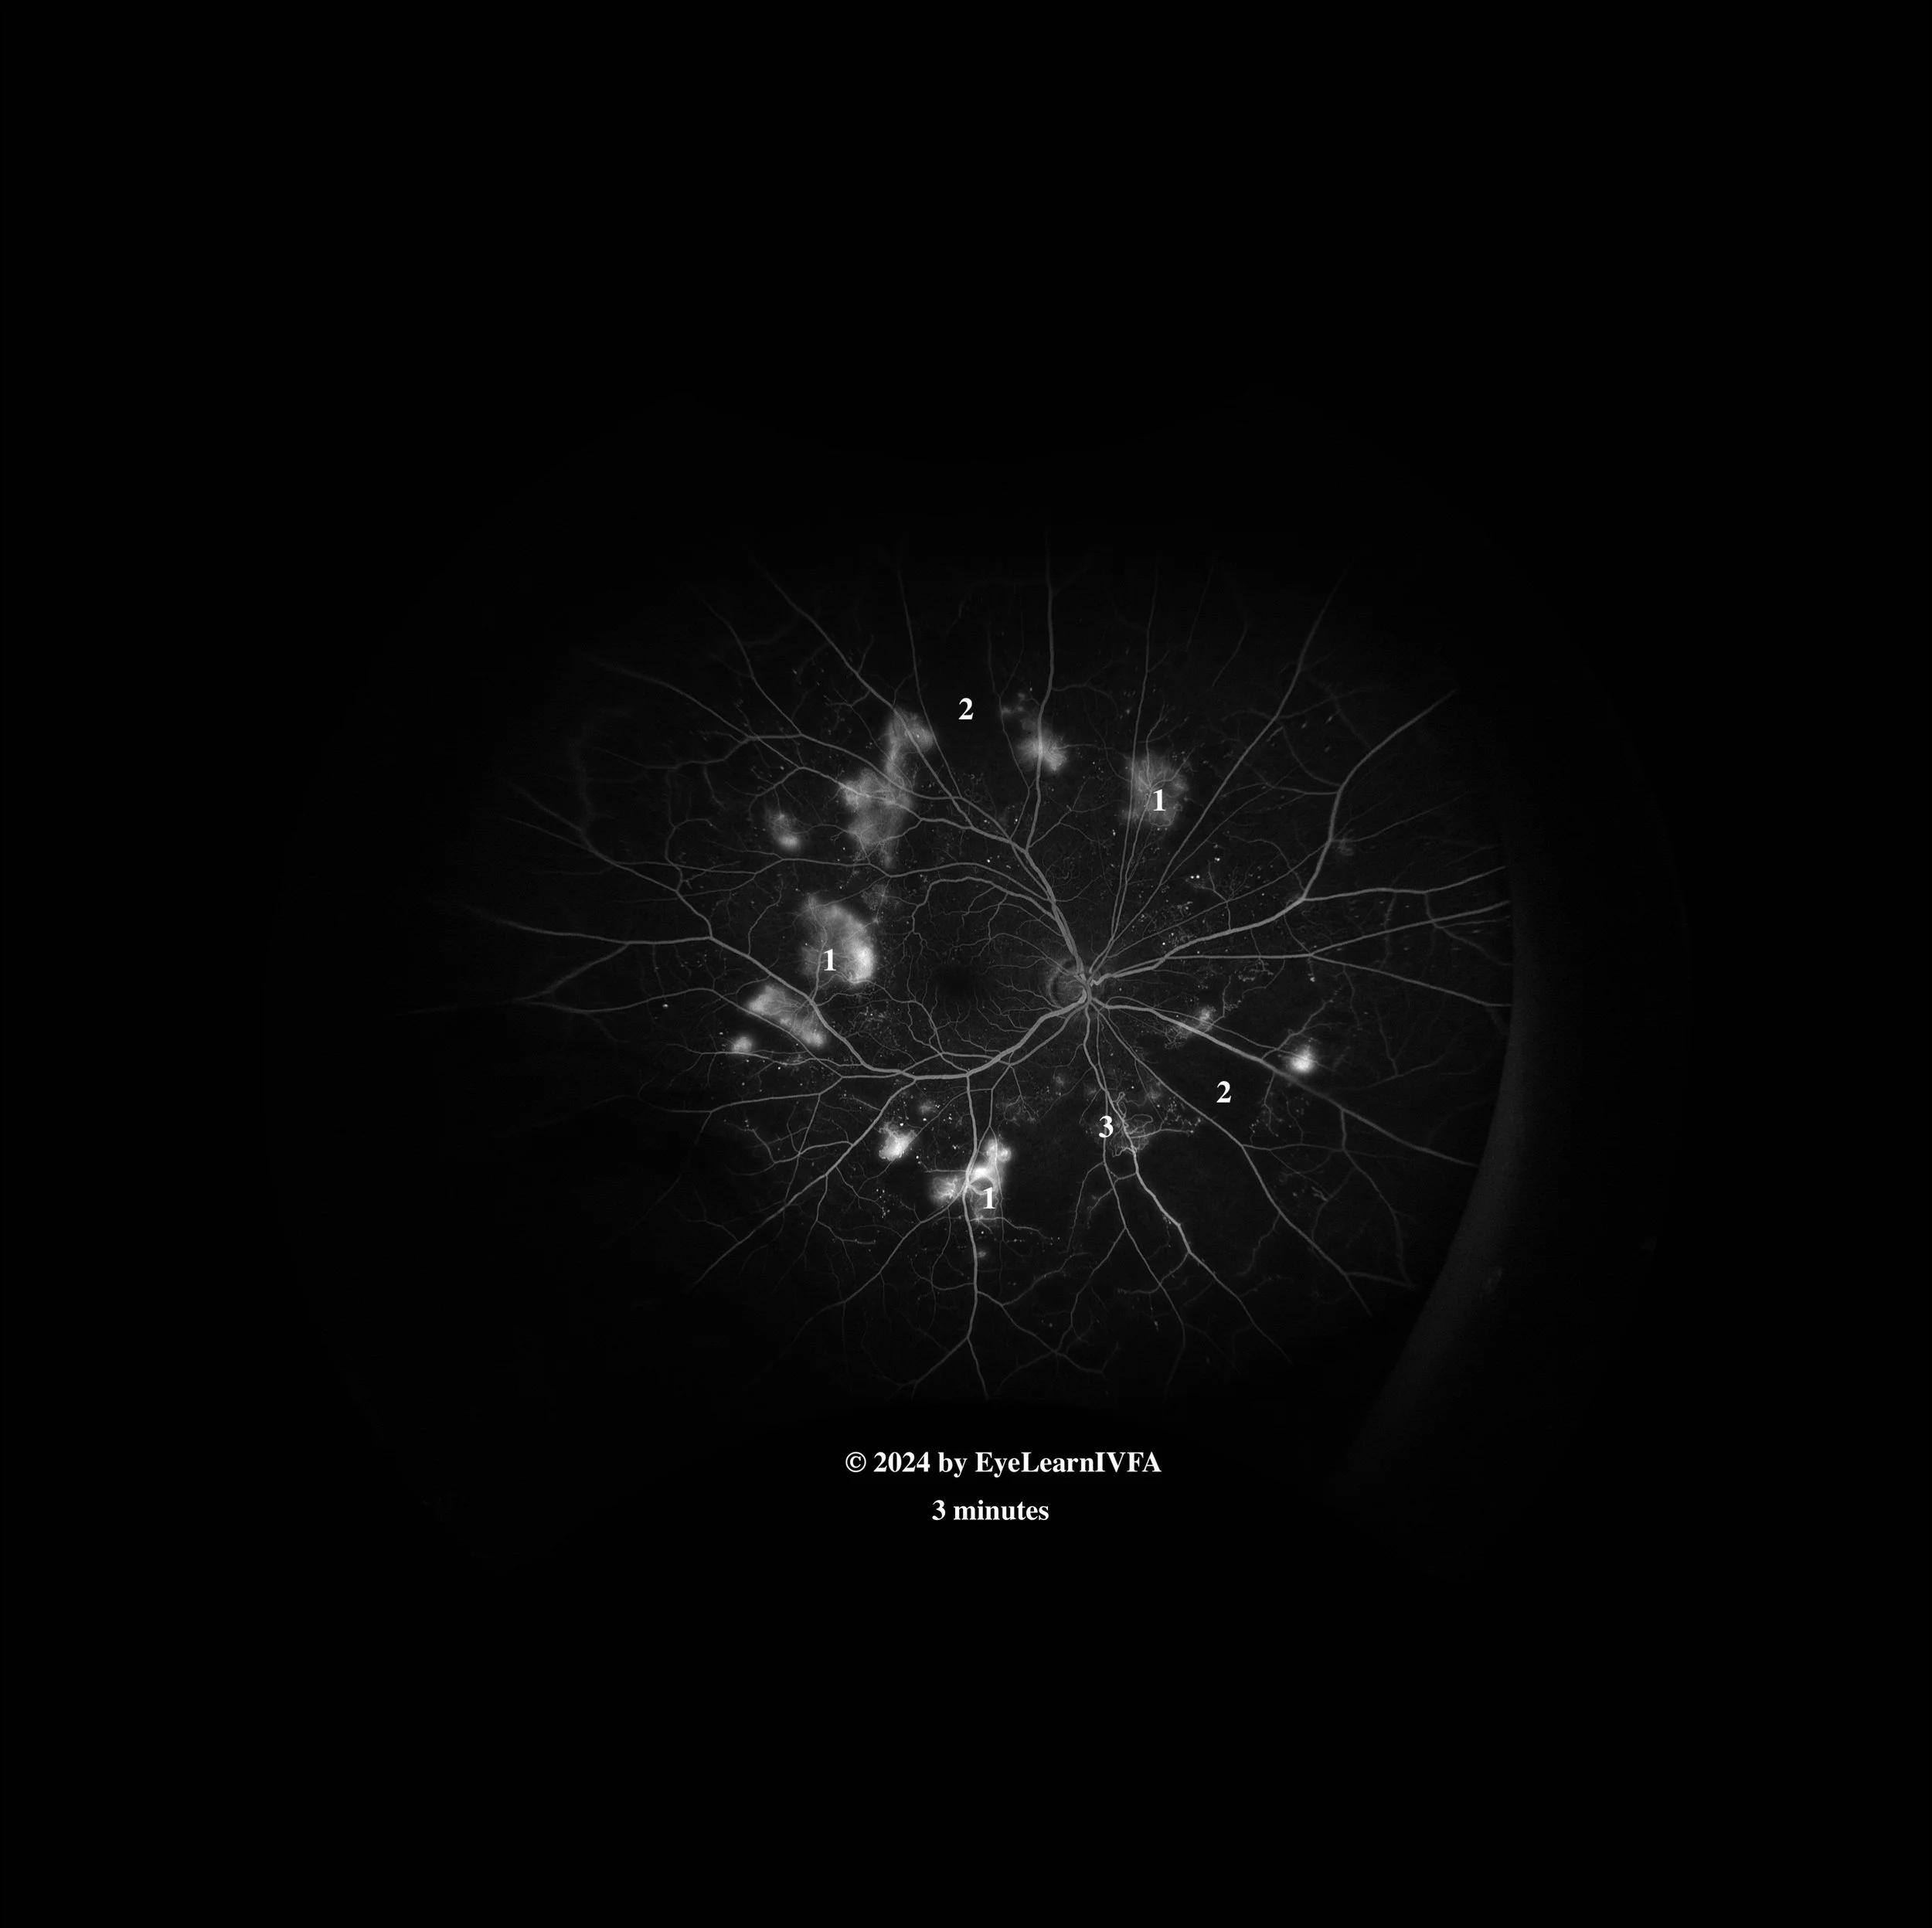

• IVFA at 3 minutes

Late phase

Key features include:

• Increasing intensity and size of hyperfluorescence characterized by indistinct borders at areas of NVE secondary to leakage. Notice how the leakage extends beyond vessel borders (1).

• Continued presence of regions of capillary non-perfusion (2) and IRMAs (3) as previously described.

• This IVFA is showing a pattern of proliferative diabetic retinopathy, highlighting areas of hypofluorescence due to retinal ischemia and areas of hyperfluorescence secondary to NVE. Many features of diabetic retinopathy in general including IRMAs and MAs are also seen in this IVFA.